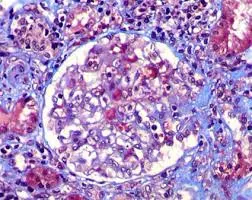

Você sabia que injeções cosméticas podem causar hipercalcemia e insuficiência renal anos após o procedimento? Descubra mais sobre os riscos e tratamentos dessa complicação em nosso novo post no blog!